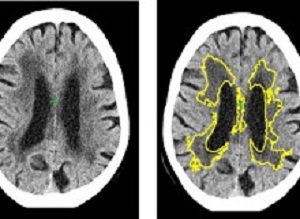

brainscansMachine learning has detected one of the commonest causes of dementia and stroke, in the most widely used form of brain scan (CT), more accurately than current methods. New software, created by scientists at Imperial College London and the University of Edinburgh, has been able to identify and measure the severity of small vessel disease, one of the commonest causes of stroke and dementia. The study took place at Charing Cross Hospital, part of Imperial College Healthcare NHS Trust.

At the moment, doctors diagnose SVD by looking for changes to white matter in the brain during MRI or CT scans. However, this relies on a doctor gauging from the scan how far the disease has spread. In CT scans it is often difficult to decide where the edges of the SVD are, making it difficult to estimate the severity of the disease, explains Bentley.

The study used historical data of 1082 CT scans of stroke patients across 70 hospitals in the UK between 2000-2014, including cases from the Third International Stroke Trial. The software identified and measured a marker of SVD, and then gave a score indicating how severe the disease was ranging from mild to severe. The researchers then compared the results to a panel of expert doctors who estimated SVD severity from the same scans. The level of agreement of the software with the experts was as good as agreements between one expert with another.

Additionally, in 60 cases they obtained MRI and CT in the same subjects and used the MRI to estimate the exact amount of SVD. This showed that the software is 85% accurate at predicting how severe SVD is.

Results: Automated WML volumes correlated strongly with expert-delineated WML volumes at MR imaging and CT (r2 = 0.85 and 0.71 respectively; P < .001). Spatial-similarity of automated maps, relative to WML MR imaging, was not significantly different to that of expert WML tracings on CT images. Individual expert WML volumes at CT correlated well with each other (r2 = 0.85), but varied widely (range, 91% of mean estimate; median estimate, 11 mL; range of estimated ranges, 0.2–68 mL). Agreements (κ) between automated ratings and consensus ratings were 0.60 (Wahlund system) and 0.64 (van Swieten system) compared with agreements between individual pairs of experts of 0.51 and 0.67, respectively, for the two rating systems (P < .01 for Wahlund system comparison of agreements). Accuracy was unaffected by established infarction, acute ischemic changes, or atrophy (P > .05). Automated preprocessing failure rate was 4%; rating errors occurred in a further 4%. Total automated processing time averaged 109 seconds (range, 79–140 seconds).